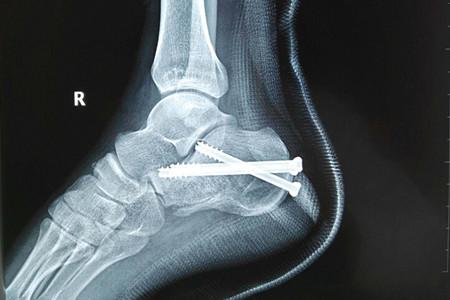

跟骨骨折以足跟部劇烈疼痛,腫脹和淤斑明顯,足跟不能著地行走,跟骨壓痛為主要表現。本病成年人較多發生,常由高處墜下或擠壓致傷。經常伴有脊椎骨折,骨盆骨折,頭、胸、腹傷。跟骨為松質骨,血循供應比較豐富,骨不連者少見。但如骨折線進入關節面或復位不良,后遺創傷性關節炎及跟骨負重時疼痛者很常見。